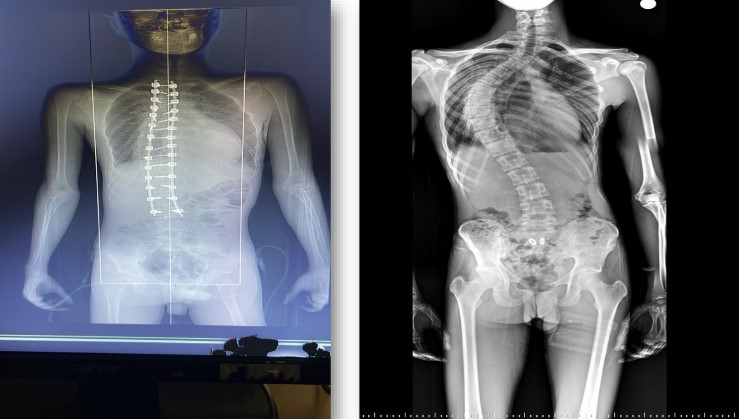

Birçok merkezde yapılamayan ileri düzey skolyoz ameliyatı, Mersin Toros Devlet Hastanesi Beyin ve Sinir Cerrahisi Uzmanı Opr. Dr. Kemal Alper Avşar ve deneyimli ameliyat ile anestezi ekibinin ortak çalışmasıyla yaklaşık 10 saat süren cerrahi müdahale sonucu başarıyla gerçekleştirildi. Tedavi amacıyla Mersin’e gelen genç hasta, yapılan muayene ve ileri tetkiklerin ardından ileri derecede skolyoz tanısı aldı. Yaklaşık dört yıldır fizik tedavi gören, ancak tüm tedavilere rağmen omurga eğriliği ilerleyen ve buna bağlı olarak ciddi solunum problemleri yaşamaya başlayan hastaya cerrahi müdahale önerildi. Ameliyat öncesi hazırlıkların tamamlanmasının ardından hasta, uzman ekip tarafından operasyona alındı.

Operasyonu gerçekleştiren Beyin ve Sinir Cerrahisi Uzmanı Opr. Dr. Kemal Alper Avşar, “İleri derece skolyoz tanısıyla il dışından hastanemize başvuran hastamızın rahatsızlığı ilk olarak dört yıl önce tespit edilmiştir. Bu süreçte düzenli fizik tedavi görmesine rağmen eğriliğin ilerlemesi durdurulamamış ve zamanla ciddi solunum problemleri ortaya çıkmıştır. Yaklaşık 10 saat süren başarılı bir operasyonla hastamızın skolyozu düzeltilmiştir" dedi.

Ameliyatın ardından hastanın yaşam kalitesinde belirgin bir iyileşme sağlandığını belirten Avşar, "Ameliyat sonrası boyu yaklaşık 4 santimetre uzayan, solunum problemleri belirgin şekilde düzelen hastamız, operasyonun ardından 10 gün içinde şifa ile taburcu edilmiştir. Pek çok hastamızda olduğu gibi bu hastamız da ameliyat ve ameliyat sonrası tüm sağlık hizmetlerinden herhangi bir ücret ödemeden, devletimizin sunduğu imkanlar sayesinde yararlanmıştır" şeklinde konuştu.

Skolyoz, omurganın göğüs veya bel bölgesinde yana doğru eğrilmesiyle ortaya çıkan bir omurga hastalığıdır. Tek başına görülebileceği gibi, omurganın arkadan öne doğru anormal eğriliği olan kifoz ile birlikte de seyredebilir. Hastalığın erken evrelerinde korse ve fizik tedavi gibi konservatif yöntemler uygulanırken, eğriliğin ilerlediği ve yaşam kalitesini düşürdüğü durumlarda cerrahi tedavi kaçınılmaz hale gelmektedir.